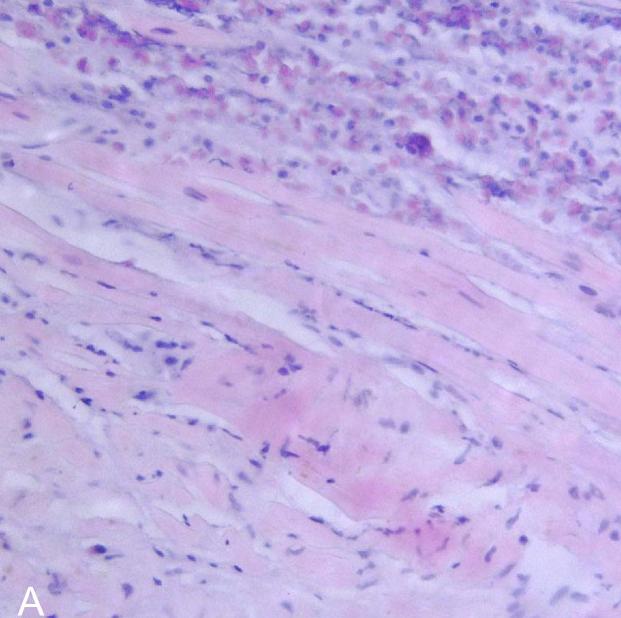

'''림프구성 심근염'''은 심근 조직에 T 세포나 B 세포 등의 림프구와 대식세포 등의 침윤을 보인다.

골드 스탠다드는 일반적으로 혈관 조영술 환경에서 수행되는 심근의 생검이다. 심내막과 심근의 작은 조직 표본을 채취하여 검사한다. 심근염의 원인은 생검으로만 확인할 수 있다. 심내막 심근 생검 표본은 조직 병리학(현미경으로 조직이 어떻게 보이는지)에 대해 평가된다. 심근 간질은 부종과 림프구 및 대식세포가 풍부한 염증 침윤을 나타낼 수 있다. 근세포의 국소적인 파괴는 심근 펌프 부전을 설명한다.[12] 또한 면역조직화학으로 표본을 평가하여 반응에 어떤 유형의 면역 세포가 관여하고 어떻게 분포되는지 확인할 수 있다. 또한 특정 바이러스를 식별하기 위해 PCR 및/또는 RT-PCR을 수행할 수 있다.